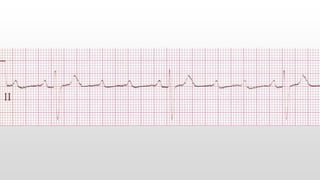

This document discusses various cases of collapse and syncope. It defines collapse as transient loss of consciousness with loss of postural tone and full recovery. Syncope is defined as loss of postural tone with or without loss of consciousness and full recovery. It then discusses the multiple potential causes of collapse and syncope including toxicological, cardiac conduction abnormalities, structural cardiac issues, autonomic dysfunction and more. It then goes through 9 case examples, discussing important questions to ask, potential tests and interventions for each case.